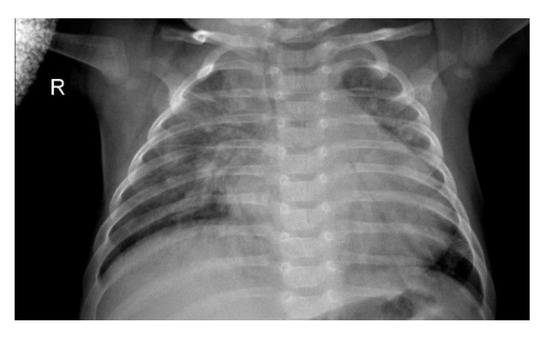

Figure 1.

Chest X-ray (CXR) image depicting pneumonia (as can be seen by inflammatory condition of lung).